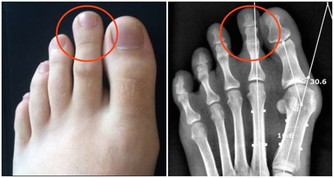

3、腿腳無病痛

如果人過了五十歲以後,腿腳還是沒有一點病痛,行動自如的,那麼說明身體各部位的器官都是正常的,如心臟、大腦、關節、肌肉等都處在正常的狀況下,這時也不會因為身體不適而導致運動量減少,從而可更好的保證身體的健康,正應了那句話“腿好腳好身體好”。